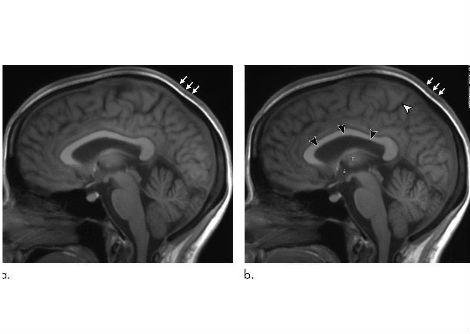

كيف تنظم خلايا الدماغ الشهية

درس الباحثون نوعين من الخلايا العصبية في دماغ الفأر:

• خلايا AgRP العصبية الموجودة في النواة المقوسة تحت المهاد (hypothalamus)، وهي المسؤولة عن تحفيز الإحساس بالجوع.

• خلايا PVH العصبية الموجودة في النواة المجاورة للبطين تحت المهاد، وهي تساعد في كبح الجوع.

تتفاعل هاتان المجموعتان من الخلايا العصبية بشكل وثيق. ففي الظروف الطبيعية، ترسل خلايا AgRP إشارات مثبطة إلى خلايا PVH، ما يؤدي إلى الإحساس بالجوع. وعندما تُثبَّط خلايا AgRP، تصبح خلايا PVH أكثر نشاطًا، مما يقلل الشهية.

وجد الفريق البحثي أن لاك-في يعمل مباشرة على خلايا AgRP ويثبط نشاطها، مما يسمح لخلايا PVH بأن تصبح أكثر نشاطًا، وبالتالي يقل تناول الفئران للطعام. والأهم أن سلوك الفئران العام لم يتأثر، مما يشير إلى أن لاك-في يقلل الشهية دون آثار جانبية سلبية.